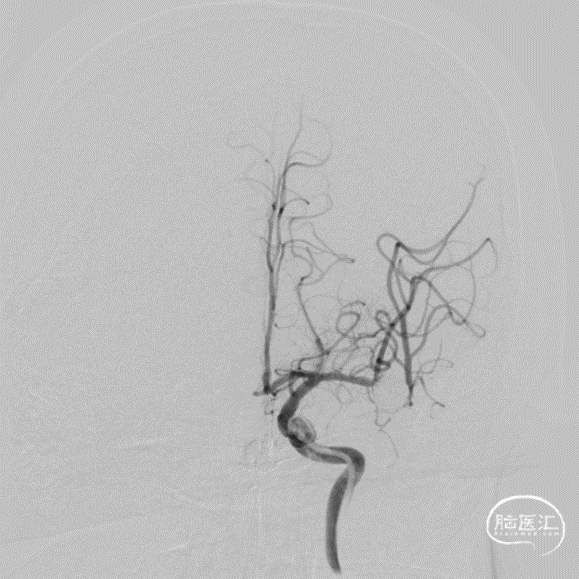

二期治疗

治疗经过